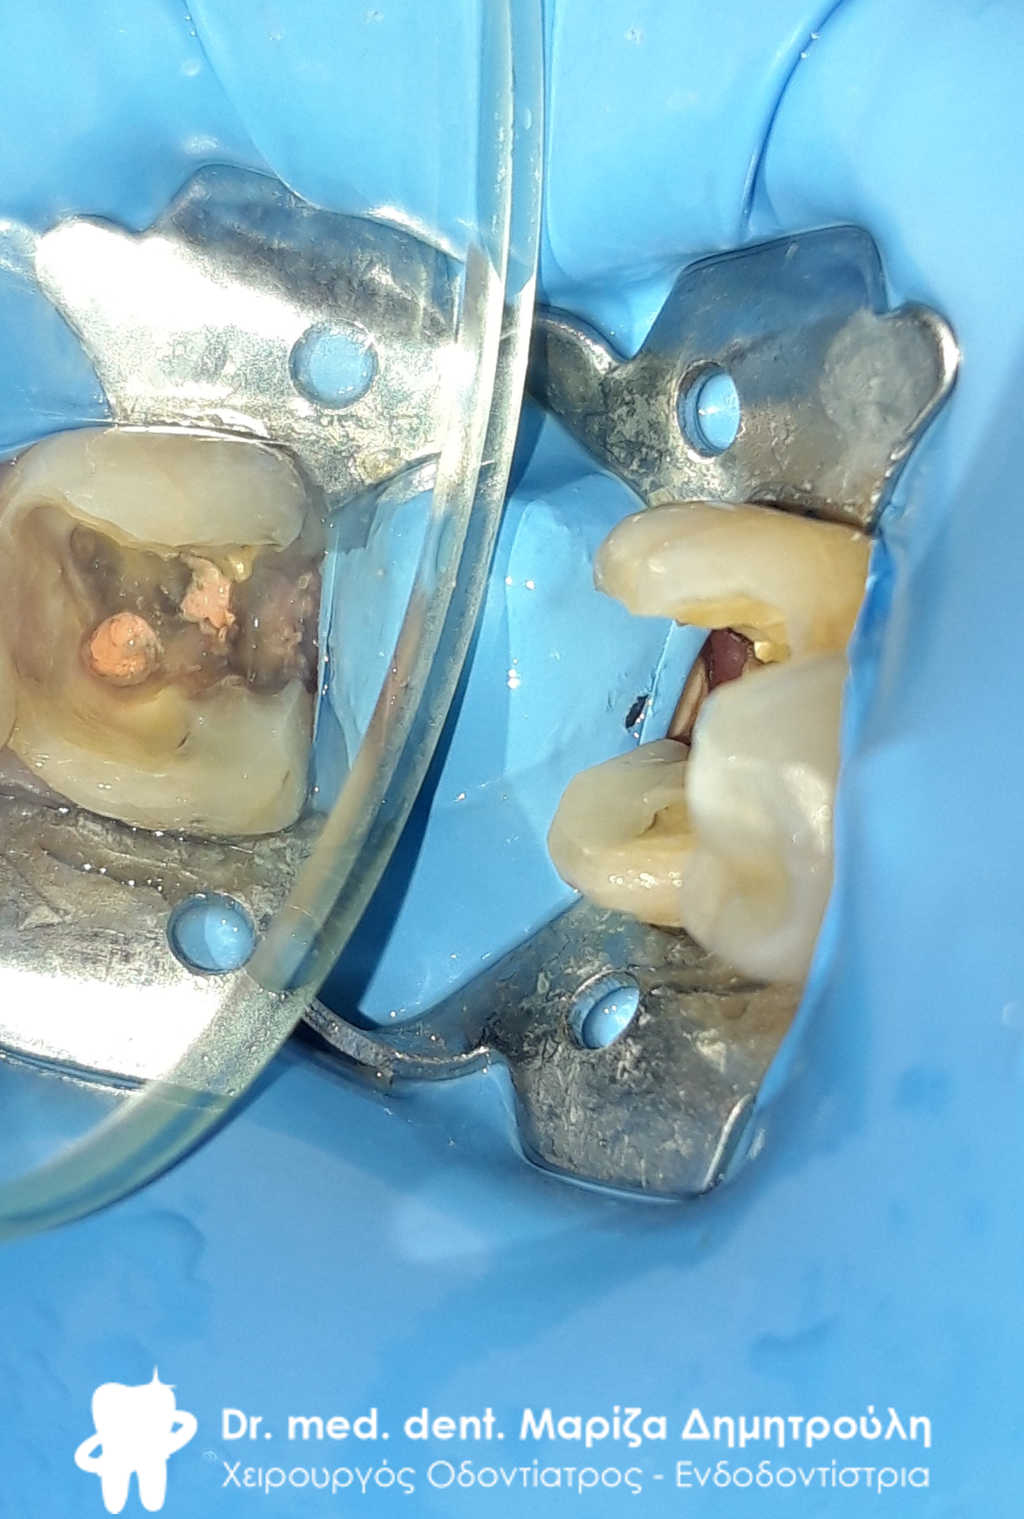

Στο συγκεκριμένο περιστατικό πραγματοποιήθηκε επανάληψη απονεύρωσης στο πρώτο δεξιό γομφίο. Στη διάρκεια της διαδικασίας εντοπίστηκε και τέταρτος ριζικός σωλήνας, ο οποίος δεν είχε βρεθεί στην πρώτη παλιά απονεύρωση. Η εγγύς ρίζα είχε ενασβεστιωθεί με τα χρόνια και δεν ήταν δυνατόν να επεξεργαστεί ο ριζικός σωλήνας σε όλο το μήκος του. Όμως όλες οι ρίζες παρασκευάστηκαν και καθαρίστηκαν πολύ καλά και στη συνέχεια εμφράχθηκαν ερμητικά.

Το δόντι με τον απομονωτήρα. Διακρίνονται 4 ριζικοί σωλήνες